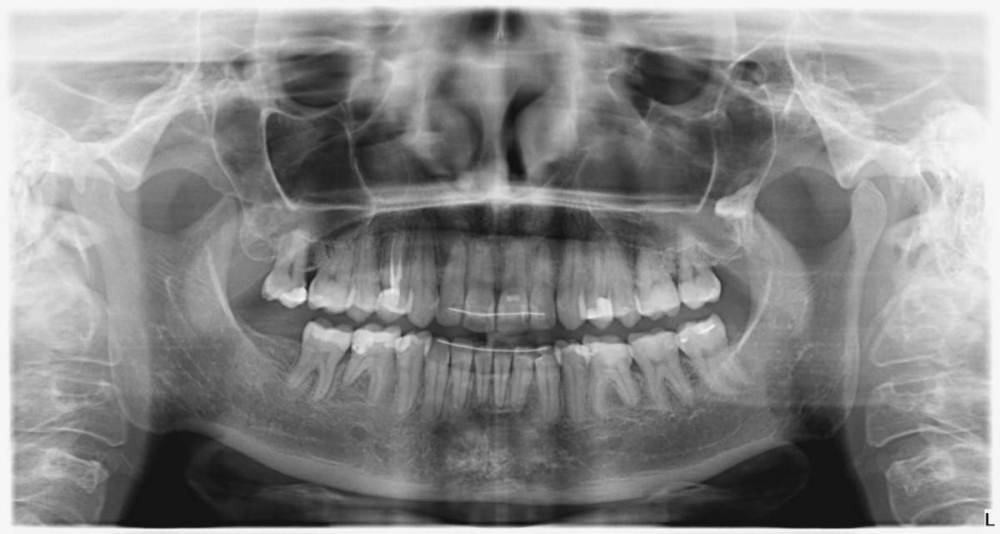

1. Посмотрите, пожалуйста, мой свежий панорамный снимок! Пожалуйста, подскажите, какие на какие области следует обратить внимание и какие требуют лечения в первую очередь.

2. Прикладываю прицельный снимок.

Можно ли по нему оценить ситуацию с кариозными областями? Или качество этого снимка оставляет желать лучшего?

Если качество прицельного снимка не очень, то тогда объясните мне, пожалуйста, для чего их делают вообще при лечении кариеса.

Американские и канадские врачи делают прицельные снимки и именно по ним приходят к окончательному выводу, где локализуется скрытый кариес (например как раз под старыми пломбами), почему у нас не так?